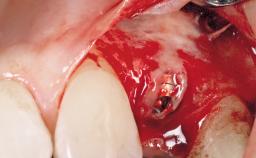

Immediate Flapless Placement of an Implant in a Maxillary Left Central Incisor Site

A 29-year-old female patient presented for treatment to replace the upper left central incisor tooth with an implant- supported restoration. The tooth had been intermittently symptomatic for the previous 12 months. The tooth had originally suffered trauma about 15 years previously. Several endodontic treatments had been performed, including an apicectomy procedure to retain the tooth. The patient was healthy and a non-smoker. She had reasonable expectations in regard to esthetic outcomes and the risk of marginal tissue recession following treatment. At medium smile, the gingival margins of the upper teeth were visible, with a display of 3 to 4 mm of the gingival margins. Gingival recession of tooth 21 and a discrepancy in the gingival levels between teeth 11 and 21 was observable during normal speech and smile.